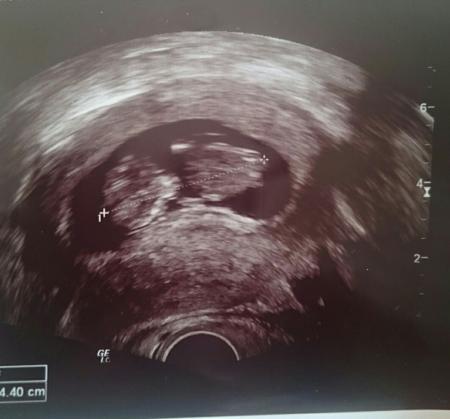

Wie sahen eure Mäuse in der 12. ssw aus

Verstehe die Frage nicht... was meinst du genau, die Größe? Die Form der Fruchthöhle? Warum brauchst du Vergleichswerte?